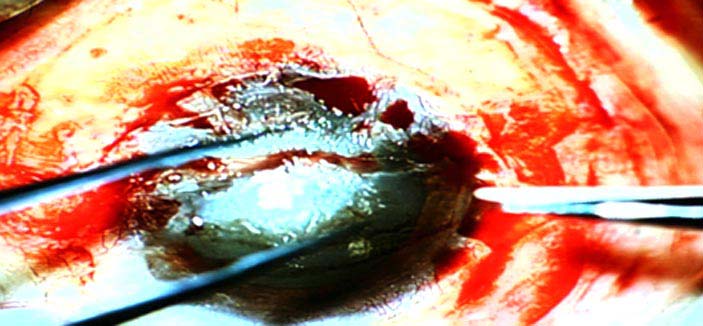

ترشيح المملكة لتكون بداية انطلاق جمعية الشرق الأوسط للقرنية برئاسة د. الطويرقي

«الجزيرة» تقف على إجراء أول عمليات زراعة الخلايا الجذعية بتخصصي الملك خالد للعيون        1 / 6 Showing image 1 of 6   الجزيرة - علياء الناجي: الجزيرة - علياء الناجي: في سابقة هي الأولى من نوعها، تقف وسائل الإعلام على أُولى عمليات زراعة الخلايا الجذعية في المملكة. وقد وقفت «الجزيرة» على إجراء العملية وزراعة الخلايا الجذعية لمريض يعاني من اعتلال بقرنيته. ووفقاً للدكتور آشلي بيرنز المدير الطبي التنفيذي بمستشفى الملك خالد التخصصي للعيون خلال تصريحه إلى «الجزيرة»، توجد دراسات مستقبلية لعلاج «الشبكية» بالخلايا الجذعية؛ إذ إنها حالياً تعالج القرنية فحسب. وأكد الدكتور بيرنز أنه يتوقع مستقبلاً أن تكون الخلايا الجذعية لعلاج أمراض عدة، مشيراً إلى وجود 100 حالة حالياً على قائمة الانتظار بالمستشفى، والمختبر الذي افتتح مؤخراً سيسهم بدوره في نقلة نوعية لعلاج القرنية بالخلايا الجذعية. وفي ظل الإنجازات المتوالية التي يحققها مستشفى الملك خالد التخصصي للعيون في زراعة القرنيات وزراعة الخلايا الجذعية، فقد تم إعلان إنشاء جمعية الشرق الأوسط للقرنية، وتم اختيار الدكتور عبدالإله بن عباد الطويرقي المدير العام التنفيذي لمستشفى الملك خالد التخصصي للعيون رئيساً لها نظراً لمكانة المستشفى العالمية، والتطور الموجود فيه، وكذلك مواكبة كل جديد في طب العيون وعدد وكفاءة عمليات القرنية والبدء في عمليات زراعة الخلايا الجذعية للقرنية وما يحظي به المستشفى من كوادر طبية وبحثية. والجمعية مفتوحة لانضمام الأطباء لها، إضافة لمجموعة الأساتذة الذين أعلنوا تأسيس هذه الجمعية. وتوجد جمعيات مماثلة في أمريكا وآسيا وأمريكا اللاتينية، الهدف منها هو تطور طب وجراحة القرنية، والتواصل مع الجمعيات المماثلة حول العالم، ودمجها تحت جمعية واحدة. وبيَّن «الطويرقي» قبول رئاسة هذه الجمعية لرفع مكانة المملكة عالمياً وإظهار ما لديها من تقدم طبي وتعليمي وبحثي في طب العيون، وذلك تزامناً مع بدء عمل مختبر الخلايا الجذعية. والأطباء الذين أعلنوا ترشيح د. الطويرقي هم الدكتورة جنيفر إيليسيف أستاذة طب العيون ومديرة مركز هندسة الأنسجة بمعهد ويلمر بجامعة جونز هوبكنز الطبية من الولايات المتحدة الأمريكية، ومن البرازيل الدكتور جوس جومنيز مدير قسم الشدفة الأمامية بجامعة ساو باولو، ومن الهند الدكتور فرندر سنجوان مدير مركز إعادة بناء سطح العين بحيدر إباد، ومن الأرجنتين الدكتور دانيل سوكورستي أستاذ ورئيس قسم طب العيون بكلية الطب بجامعة سلفادور ببوينس آيرس. من جهته، أكد الدكتور عبدالإله بن عباد الطويرقي المدير العام التنفيذي لمستشفى الملك خالد التخصصي للعيون أنه تم إجراء أول ثلاث عمليات زراعة الخلايا الجذعية للقرنية، الأولى لرجل يبلغ من العمر 58 عاماً، والثانية لشاب 28 عاماً، والثالثة لطفلة عمرها 10 أعوام، وجميعهم سعوديون، وكانت العمليات منقولة على الهواء مباشرة لقاعة المحاضرات الرئيسية بالمستشفى. وأضاف د. الطويرقي بأنه تم أخذ عينة من خلايا القرنية للمريض قبل أسبوعين، وقمنا بمتابعتها يومياً في المختبر الخاص بالخلايا الجذعية حتى نمت، وتم بعدها إخضاع المريض المستفيد للجراحة، والحمد لله تكللت العملية بالنجاح بفضل الله، وهذا الإنجاز الطبي متميز على مستوى الشرق الأوسط، ونحن سعداء بأن يضاف مثل هذا الإنجاز لاسم مملكتنا الحبيبة. وقال الدكتور الطويرقي إن نتائج العملية ستكون بعد أسبوعين تقريباً من اليوم، وإن شاء الله النتائج مبشرة. وأضاف: المستشفى بحسب مكانته المتميزة بين مستشفيات العيون في العالم لديه بنك العيون الذي يعتبر فريداً من نوعه، ليس في المملكة فحسب بل في الشرق الأوسط كافة. ومختبر الخلايا الجذعية للقرنية الأول من نوعه في الشرق الأوسط، وهو موجود في بعض الدول الأوروبية واليابان وبعض دول أمريكا اللاتينية. |